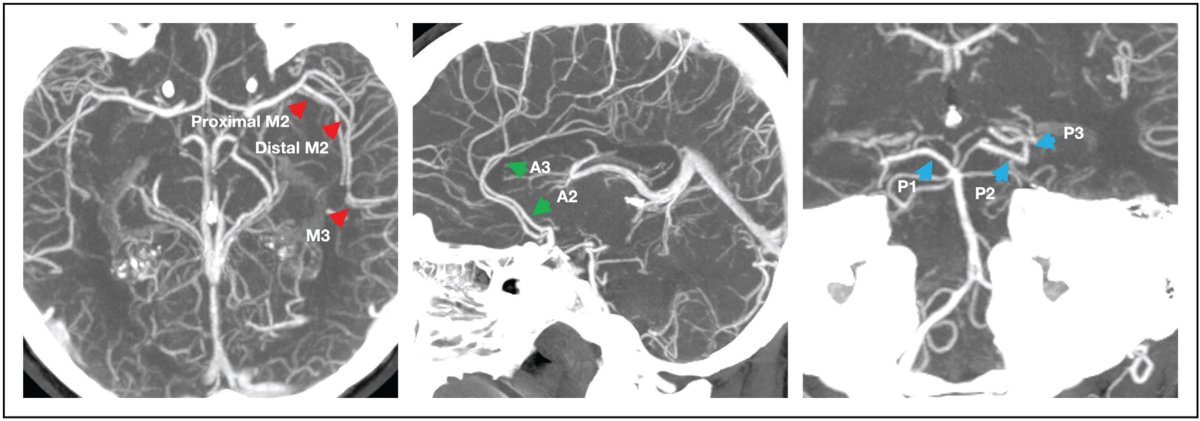

👀A pictorial #MeVO case review🖼️with discussion of state of the art evidence: superbly written by A. Ciacciarelli and G. Busto🤩 #INR #stroke #neurorad ➡️ rdcu.be/e6MIa